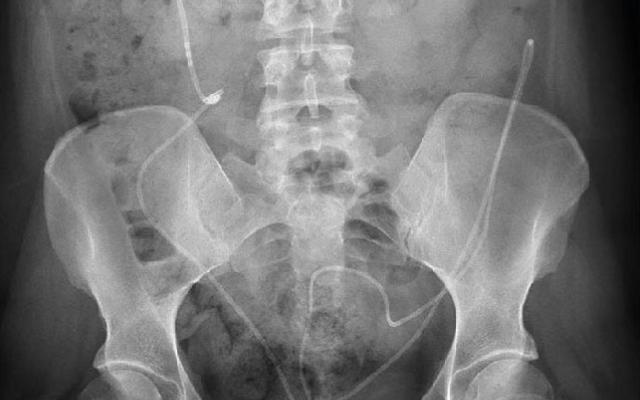

Fissura ani: laterale sfincterotomie of dilatatie van de anus?